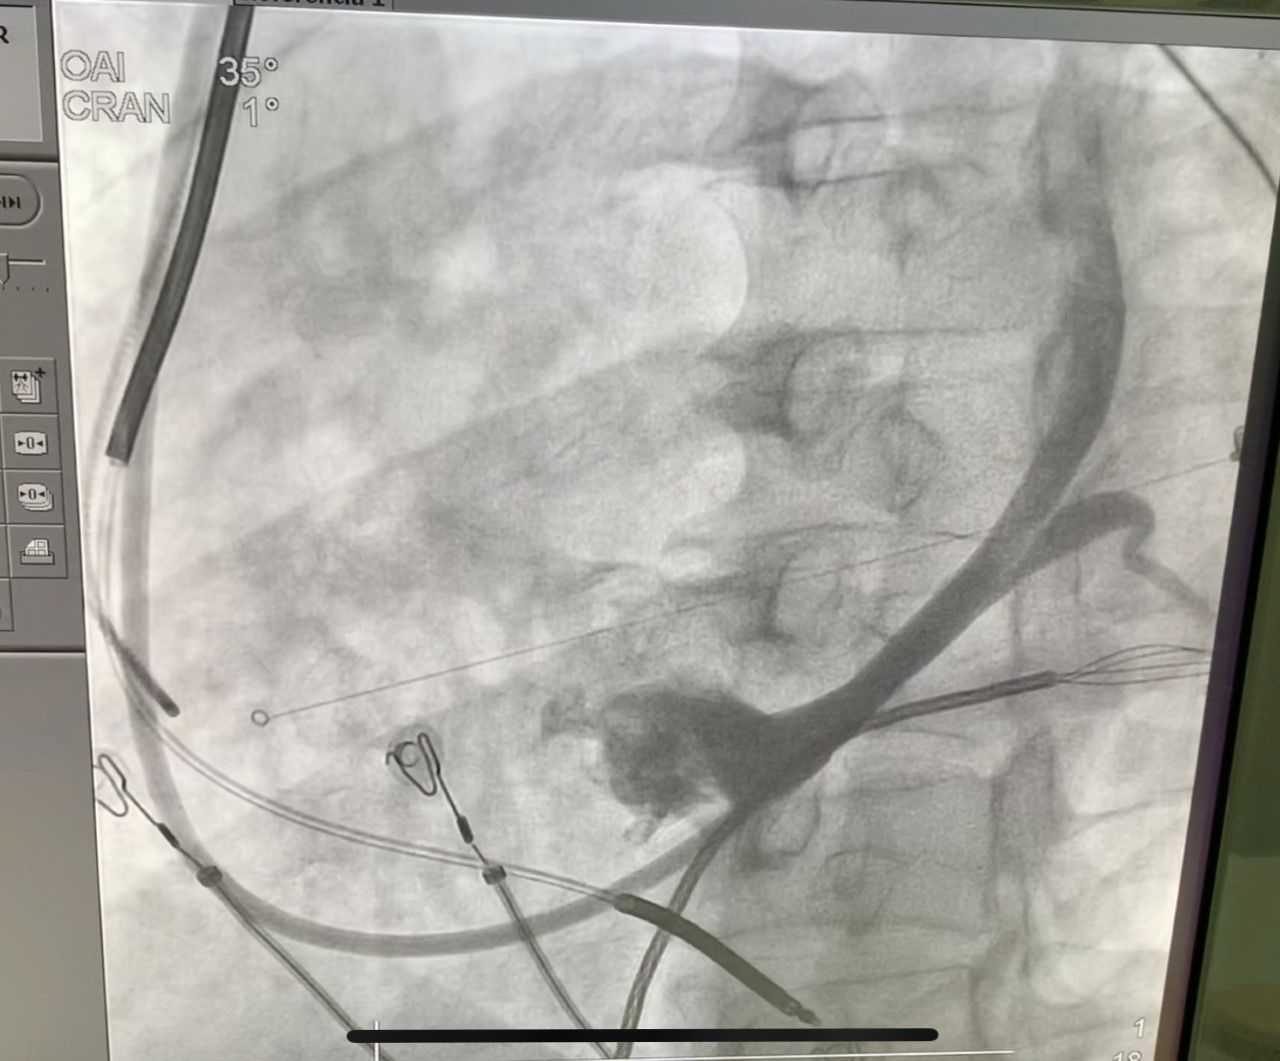

Realicé mi formación como médico general en la Universidad Autónoma de Veracruz Villa Rica, posteriormente la especialidad en medicina interna durante dos años en centro medico nacional Adolfo Ruiz Cortinez UMAE 14 en Veracruz, recibiendo en el primer año el reconocimiento por excelencia académica y en el segundo año reconocimiento al mejor promedio de mi generación. Realicé la subespecialidad en Cardiología clínica en el Centro Médico Nacional “La Raza”, en la Ciudad de México siendo jefe de residentes en el último año de la residencia médica, durante el tiempo la sede recibió el premio a la mejor cede de formadores de cardiología 2012-2013 premio otorgado por Dr. Enrique Graube (en ese entonces Director de medicina UNAM). Entre mis actividades asistenciales y conferencias, he presentado trabajos libres a nivel internacional (congreso de falla cardiaca lisboa 2013, Congreso mundial de cardiologia 2016, 2018 en AHA) ganador del premio internacional “la imagen más bella en cardiología, sociedad europea cardiologia España 2013”, así mismo presentación de más de 35 articulos publicados en revistas indexadas, soy miembro de la sociedad mexicana de cardiología no. 2076, asociación mexicana de cardiología, Fellow in training de la American collegue of cardiology capítulo México. Miembro de la sociedad europea de cardiología ESC ID 509395. Médico adscrito en el centro médico nacional la Raza, fui profesor adjunto del curso de cardiología en el mismo centro y sindal en el exámen de certificación de cardiología clínica de la sociedad mexicana de cardiología. Desde el 2016-2018 realicé curso de alta especialidad en electrofisiología cardiaca y estimulación cardiaca , realizando cursos fuera del país para especialización en técnicas avanzadas de ablación de arritmias, actualmente me encuentro realizando en el segundo año de la maestría en Dirección y Gestión de Instituciones de salud y Especialidad en Gestión de la Salud y Bienestar Corporativo

• TAVI ( implantacion percutanea de válvula aórtica)